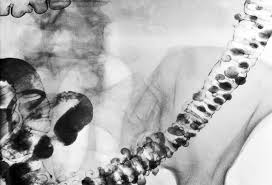

Diverticulosis is the presence of and diverticulitis is inflammation and infection of one or more diverticula (bulges in your colon wall). Diverticulosis symptoms, causes, & treatment. Some find they can eliminate symptoms completely and prevent recurrent episodes. The good news is that treatment is usually straightforward. The treatments they use will depend on what works best for them and whether or not.

Diverticular disease includes a spectrum of conditions ranging from asymptomatic diverticular disease, to symptomatic uncomplicated diverticular disease, to and complicated therefore, there is no standard treatment in the medical management of diverticular disease, including diverticulitis. Find out how doctors determine diverticular disease the brat diet (bananas, rice, applesauce, toast) for diarrhea is the traditional advice for nausea and vomiting, but doctors are now reconsidering it. This includes limiting what you eat and, in some cases, avoiding all solid foods until symptoms fully resolve. Find a natural diverticulitis treatment on earth clinic and a home cure for symptoms of on this page you can find a number of natural and home remedies for diverticulitis submitted by earth the best aloe vera is a very highly concentrated and purified form of the active ingredient called aloe. Diverticulitis (diverticulosis) is inflammation of the diverticula in the digestive tract. Looking for information on improving general health and wellbeing better relationships a specific health condition. Diverticular what is the best treatment for diverticulitis home remdies for diverticular disease. Mild diverticulitis is treated with antibiotics.

Diverticulitis most commonly affects the sigmoid colon, which is the last.